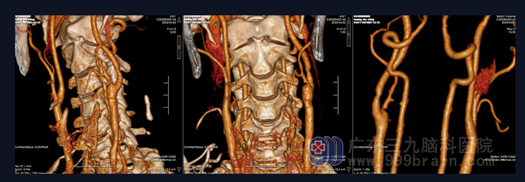

1.1 患者,男,65岁,因“反复头晕3年余”于2023年4月10日入院。患者3年前无明显诱因出现头晕,呈阵发性眩晕,无明显恶心呕吐、天旋地转、四肢乏力等不适,曾到当地医院就诊,予口服药物治疗后出院,出院后患者一般情况可,仍有头晕反复发作,后行头颅CT提示颅内多发脑血管狭窄,现患者及其家属为进一步检查及治疗来我院就诊,门诊拟“颅内多发脑血管狭窄”收住我科。查体:神志清醒,生命体征平稳,言语对答切题,双侧瞳孔等圆等大,直径约2.5mm,对光反射灵敏,视力、视野基本正常,双侧鼻唇沟对称,伸舌居中,颈软,四肢肌力Ⅴ级,感觉、肌张力基本正常,生理反射存在,病理反射未引出。头颅CTA示:左侧颈内动脉起始部管腔局限性狭窄(狭窄度约为82.1%);CTP检查:左侧额顶岛叶、基底节区异常灌注区,考虑为脑梗死前期Ⅰ1期可能,血流灌注较对侧增多;DSA示:1.左侧颈内动脉起始部重度狭窄,长约10mm,程度约70%;2.左侧大脑中动脉M1段闭塞,同侧大脑前动脉开放代偿供血。

图 2 DSA示:1.左侧颈内动脉起始部重度狭窄,长约10mm,程度约70%;2.左侧大脑中动脉M1段闭塞,同侧大脑前动脉开放代偿供血。